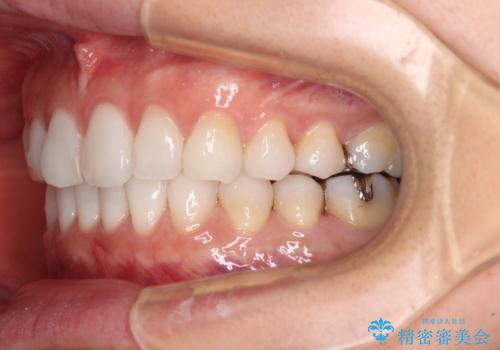

- 前歯のデコボコを気にして来院された患者様です。

海外に留学をされており、卒業後はしばらく日本にいるものの、再び就職のため出国するとのことでした。

定期的に日本に戻ってくる予定であるため、来院頻度の少ないインビザラインにて矯正治療を行うこととしました。

歯列不正が軽度であり、インビザラインの装着時間を遵守してくださったため、日本と海外を行き来しながらも2年弱でしっかりと仕上げることができました。